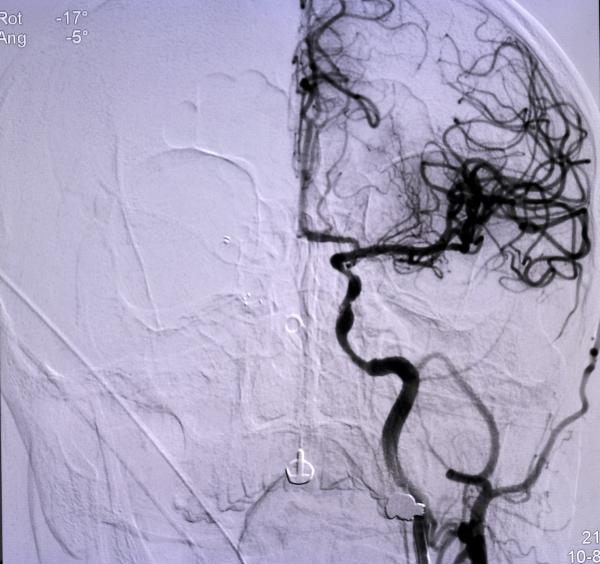

Niğde’den ellerinde uyuşma şikayeti sonrası başvurduğu hastaneden Konya’ya sevk edilen Ömer Altan’ın (73), kısa sürede müdahalesi yapılarak, tıkanan ana damarını açtıklarını belirten Doç. Dr. Gökhan Özdemir, “Hastamız Niğde şehrinden bize başvurdu. Oradaki hekim arkadaş hastayı değerlendirdi. Beyni besleyen ana büyük damarında ciddi bir darlığı tespit etti. Bu da hastanın felç geçirmesine sebep olan bir durum. Oradaki doktor arkadaş hızlıca bize ulaştı ve biz de hastayı kabul ettik. Bekletmeden burada hastanın müdahalesini yaptık, ana damarını açtık. Ana damar olduğundan dolayı bu hastaların büyük bir kısmı ölüyor. Yani beyni besleyen ana büyük damarlardan biri tıkandığı zaman genelde bu hastanın yüzde 50-60’ı ölüyor. Ölmese bile büyük ihtimalle ömür boyu özürlü kalacaktı” dedi. (DHA)

FOTOĞRAFLI